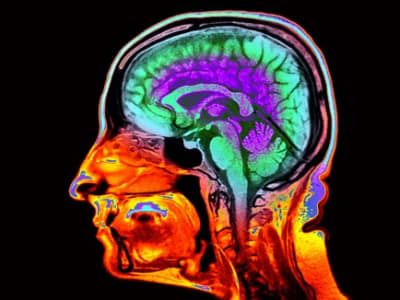

Courtesy of NatureMagazine

Santiago, Chile - Penelitian terbaru menunjukkan bahwa melakukan aktivitas kreatif seperti menari tango, bermain gitar, atau melukis dapat membantu menjaga otak tetap muda. Otak para ahli dalam bidang ini tampak lebih muda dibandingkan dengan usia sebenarnya, menunjukkan efek perlindungan dari kegiatan tersebut.

Studi ini menggunakan alat ukur bernama brain clocks yang membandingkan usia kronologis seseorang dengan usia otaknya yang terlihat berdasarkan scan otak. Aktivitas kreatif meningkatkan koneksi dalam bagian otak yang biasanya cepat mengalami penuaan, seperti wilayah frontoparietal.

Para peserta yang sudah ahli dalam bidang kreatif cenderung memiliki otak yang lebih muda. Tango khususnya memberikan efek terbesar, karena melibatkan koordinasi, perencanaan, dan gerakan yang kompleks, membuat otak mereka tampak hingga tujuh tahun lebih muda.